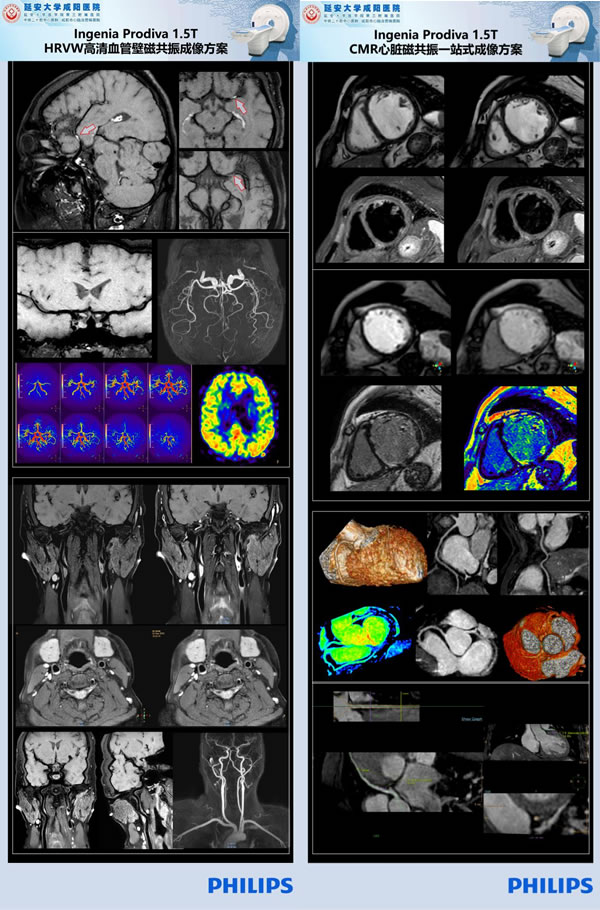

近十年來隨著磁共振成像技術(shù)的飛速發(fā)展,磁共振成像在心臟、大血管方面的應(yīng)用價值越來越受到臨床的認(rèn)可,甚至是依賴,心臟磁共振成像(Cardiac magnetic resonance imaging,CMRI)已經(jīng)成為臨床心臟高端檢查之一。CMRI一次檢查即可以獲得心臟的解剖、功能、灌注、代謝及冠狀動脈分布等綜合信息,可以通過常規(guī)序列顯示心臟的大體形態(tài);通過電影序列評估心肌功能;可以通過首過灌注及延遲強(qiáng)化診斷心肌疾?。徊⑶掖殴舱襁€可以通過定量技術(shù),反映組織特征,即所謂“一站式”心臟檢查。

延安大學(xué)咸陽醫(yī)院CT/MRI室在院長助理兼影像科主任劉連鋒教授帶領(lǐng)下,引進(jìn)先進(jìn)飛利浦1.5T Prodiva設(shè)備,通過不斷的學(xué)習(xí)研究,歸納總結(jié),將高分辨磁共振血管壁成像這一項(xiàng)目由稚嫩發(fā)展至成熟的同時還在磁共振心臟、冠脈成像技術(shù)領(lǐng)域取得了重大突破,對掃描及診斷缺血/非缺血性心肌病、心包疾患、心臟瓣膜病及大血管病變等疾病篩查上邁出了關(guān)鍵性的一步!這項(xiàng)舉措不僅極大推動了1.5T磁共振心臟、冠脈成像技術(shù)在省內(nèi)的開展,也是咸陽市三甲醫(yī)院開展此項(xiàng)目先例!